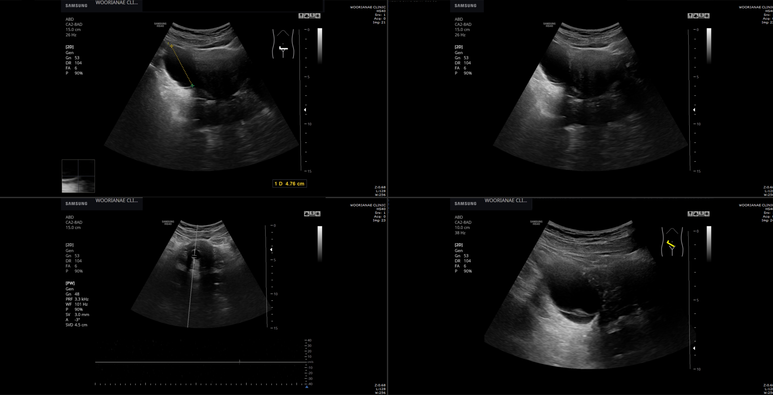

초음파상 오른쪽 난소에 5 cm이상의 cyst, 물혹과 자궁 경부쪽에 nabothian cyst, 나보트 낭종이 관찰되어 산부인과 추적 계획